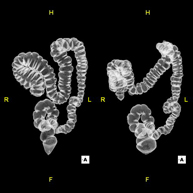

Virtual colonoscopy is a non-invasive technique that allows three-dimensional and two-dimensional visualisation of the large intestine or colon by taking sequential images captured with a state-of-the-art MDCT scanner. The quality of the images allows virtual navigation through the rectum and colon thanks to processing on specialised workstations. Preparation for the test consists of following a low-fibre diet for three days before the test (to cleanse the colon and rectum) and ingesting an iodinated oral contrast agent the day before the test (to mark the stool so that it can be correctly distinguished from any colonic lesions). Unlike fibrocolonoscopy, no sedation or bowel preparation is required. The test is performed in the CT room, where air is blown through a small flexible tube to distend the colon.